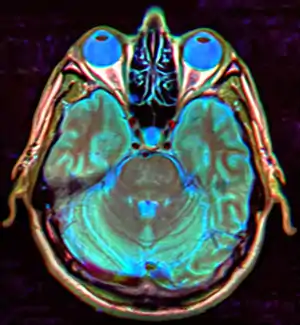

| Diagnostic method | MRI, CT scan[1] |

The major differential to consider in empty sella syndrome is intracranial hypertension, of both unknown and secondary causes, and an epidermoid cyst, which can mimic cerebrospinal fluid due to its low density on CT scans, although MRI can usually distinguish the latter diagnosis.[11]